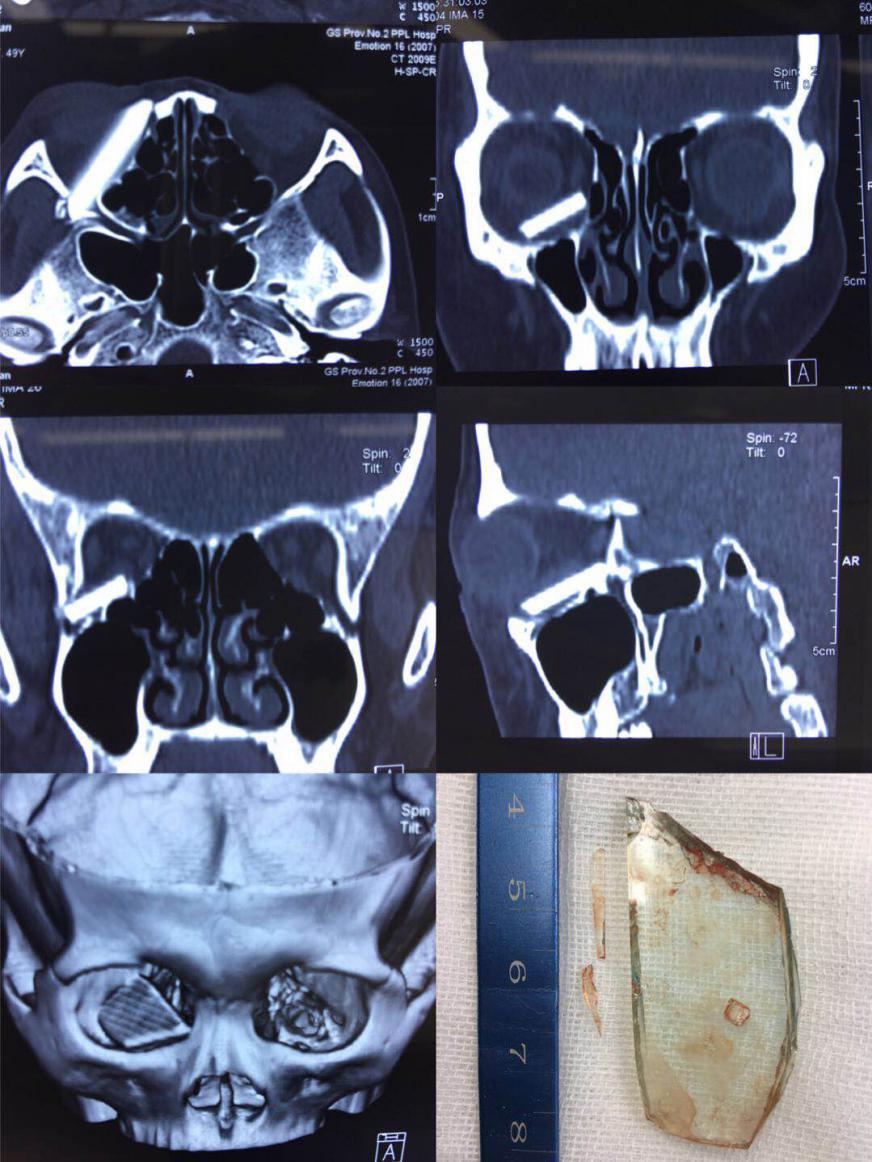

患者,女,48岁,因"右眼外伤4天"以"右眼眶异物"于2018年8月31日转入我院眼科。患者在家擦玻璃时玻璃破碎伤及右眼,在当地清创缝合,拍CT发现"右眼眶内异物"伤后4天转我院。入院时查,视力右眼4.8,左眼4.9,右侧面部肿胀,右眼上下睑肿,右眼眶下缘类三角皮肤裂口(己缝合),眶下神经感觉异常,眶压稍高,眼球向上移位,向上下转动受限,球结膜充血水肿,穹窿部结膜裂伤,余眼前后节无明显异常。CT显示右眼眶底类长方形异物,异物刺穿眶外侧壁。入院后全麻下行眶内异物取出并眶壁修复术,术中取出约4*2.5大小的玻璃异物及小玻璃碎片,缺损眶壁钛板修复。术后次日查,视力同前,眼位正常,眼球上下转动稍受限。

对此病例很有感概,如此大的玻璃异物刺入眼眶未伤及眼部主要功能实属奇迹,同时惊叹眶内眼球、血管、神经对外来“侵略者”的神奇回避能力。该患者非常幸运,因为异物进入的线路恰好是最不伤害眼眶组织的地方,如果方向稍向内偏一点点,必伤及眶下裂,更堪者可能伤及眶上裂及视神经,后果不敢想象。